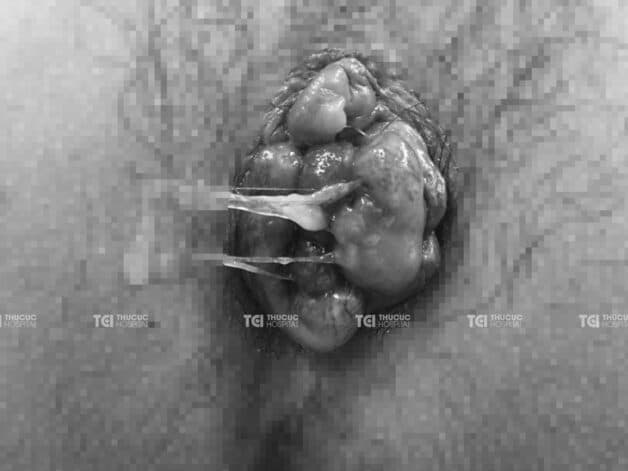

Hình ảnh búi trĩ gây tắc mạch, hoại tử